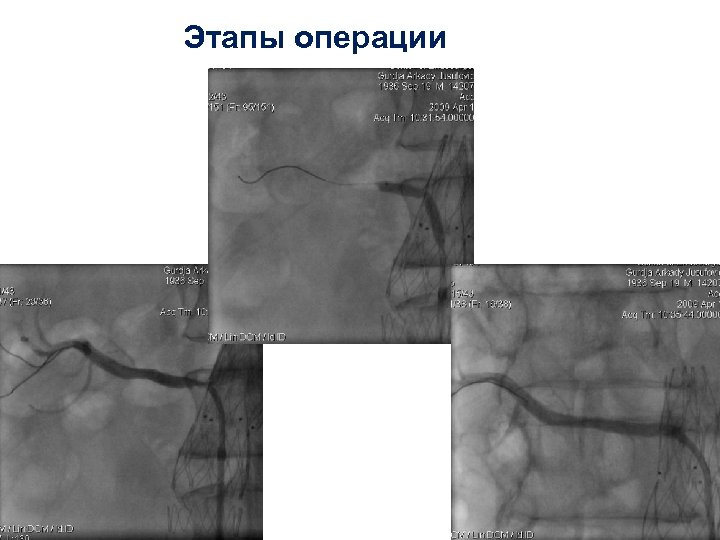

Этапы операции

Этапы операции